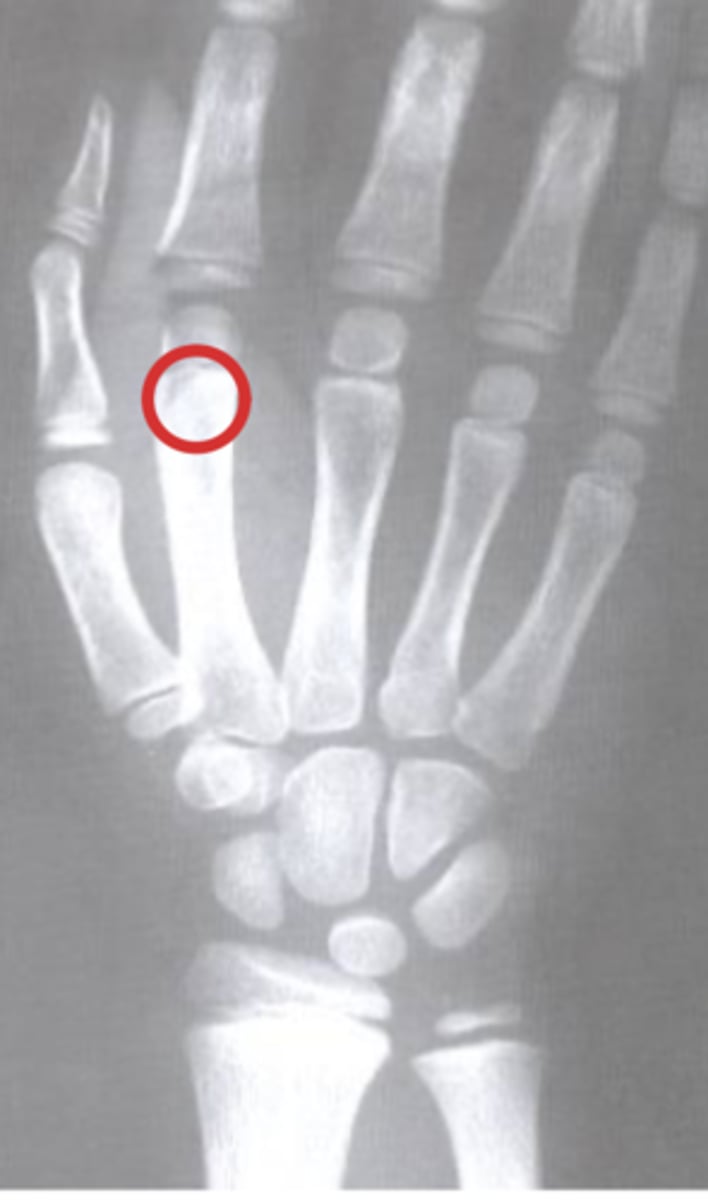

Ganglion cyst

What is the issue?